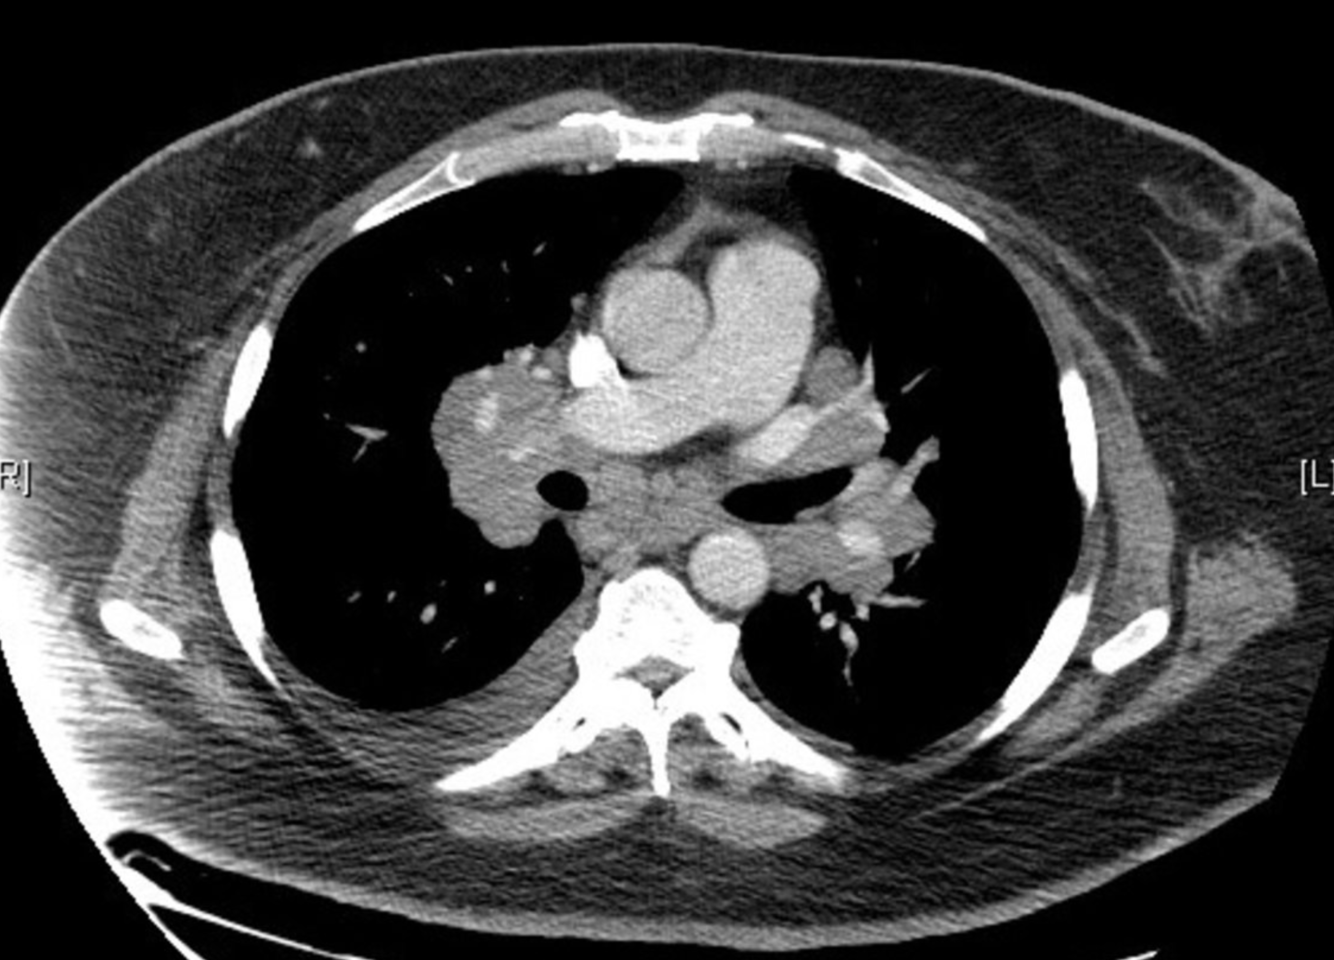

Sarcoidosis

CT of the thorax (axial view)

Bilateral hyperdensities in the areas of the mediastinal and hilar lymph nodes can be seen (green overlay).

There is also evidence of right-sided pleural effusion (red overlay).

This is the typical appearance of bilateral lymphadenopathy, a common finding in sarcoidosis.